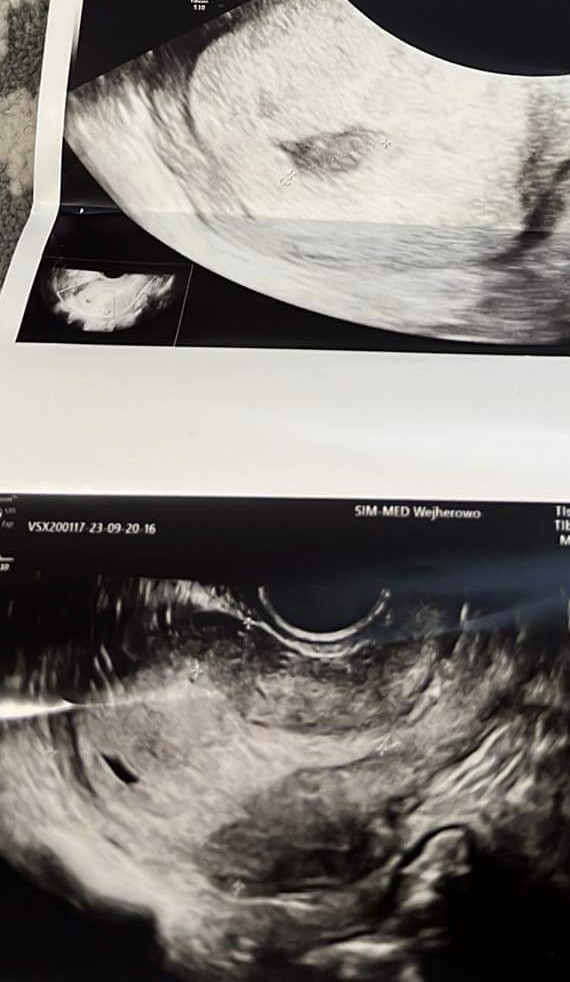

Nieregularny pęcherzyk ciążowy

Lekarz stwierdził wczoraj nieprawidłowy pęcherzyk ciążowy- jego kształt. Czy ktoś miał podobnie ?

Czy któraś z Was miała podobny pęcherzyk?

Lekarz stwierdził tylko, ze nie wie co ma o tym myśleć… bo jest duży i nieregularny…

Mam krwiak 17mm, raz poleciała mi krew, ale serduszko zaczęło bić.

2 tyg temu pęcherzyk ciążowy był okrągły, a teraz jest taki dziwny :(

6t4d, CRL 0,67cm, biorę luteinę i neoparin